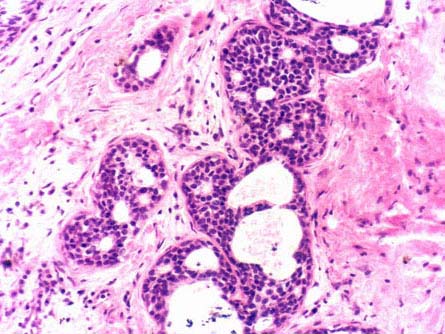

[单选题]患者女性,45岁。左乳腺包块2年,镜检如图所示乳腺小叶导管和腺泡上皮细胞的增生、导管囊状扩张,层次增多,轻度异型,局部呈筛状结构,间质纤维组织增生。则该病变的诊断是()A . 乳腺纤维腺瘤B . 乳腺小叶癌C . 乳腺增生性纤维囊性变D . 浸润性导管癌E . 硬化性腺病